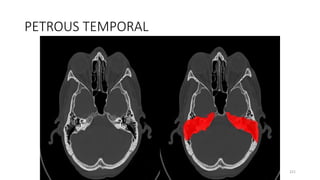

PETROUS PART OF TEMPORAL BONE

PETROUS TEMPORAL